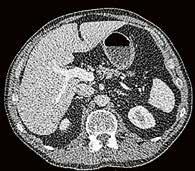

Fall 1:

Biphasische Abdomen-CT bei einer deutlich adipösen Patientin. Hier lässt sich sowohl Dosis sparen als auch die Qualität der Rekonstruktionen verbessern. Beispielsweise findet sich deutlich weniger Bildrauschen, insbesondere im Bereich der parenchymatösen

Fall 2:

Portalvenöse Abdomen-CT. Auch hier ist die Dosis am Aquilion Prime SP mit AiCE geringer, zudem auch hier geringeres Bildrauschen mit sehr guter Abgrenzbarkeit, beispielsweise von Leberläsionen.

Abb. 1 a: biphasische Abdomen-CT, Canon Aquilion Prime, Rekonstruktion: AIDR 3D; DLP 1003,6 mGy × cm / 18,1 mSv. Abb. 2 a: biphasische Abdomen-CT, Canon Aquilion Prime, Rekonstruktion: AIDR 3D; DLP 1003,6 mGy × cm / 18,1 mSv. Abb. 1 b: biphasische Abdomen-CT, Canon Aquilion Prime, Rekonstruktion: AiCE; DLP 716,5 mGy × cm / 12,9 mSv. Abb. 2 b: biphasische Abdomen-CT, Canon Aquilion Prime, Rekonstruktion: AiCE; DLP 716,5 mGy × cm / 12,9 mSv. Oberbauchorgane.

22 // VISIONS 31

Fall 3:

Thorax-CT im Rahmen einer Lungenkrebsfrüherkennungsstudie. Die Voruntersuchung lag als externe kontrastmittelgestützte Thorax-CT vor. Bei der dosisoptimierten Low-Dose-CT liegt die Strahlenexposition nur noch im Bereich von zwei konventionellen Röntgenaufnahmen des Thorax, die Bildqualität ist für die Fragestellung nach Herdbefunden aber dennoch eindeutig ausreichend, selbst interstitielle Lungenveränderungen lassen sich hier noch beurteilen.

„KI-basierten Rekonstruktionen im Clemenshospital nun fester Bestandteil der Standardprotokolle.“

Prof. Dr. med. Johannes Weßling Zentrum für Radiologie, Neuroradiologie und Nuklearmedizin Abb. 3 a: kontrastmittelgestützte Thorax-CT, externe Untersuchung; DLP 216,0 mGy × cm / 3,9 mSv. Abb. 3 b: dosisoptimierte Low-Dose-Thorax-CT, Canon Aquilion Prime SP, Rekonstruktion: AiCE; DLP 13,9 mGy × cm / 0,25 mSv.

VISIONS 31 // 23 © 2021 C ANON MEDICAL SYSTEM S

Low-Dose-Thorax-CT als Verlaufskontrolle bei Lungenkarzinom unter Immuntherapie. Aus der Anfangsphase der Implementierung von AiCE im klinischen Alltag zeigt sich bei vergleichbarer Dosis eine bessere Bildqualität mit besserer Detailauflösung im Bereich des Lungenparenchyms, hier im Bereich der strahligen Ausläufer des Tumors und an den direkt angrenzenden Bronchialstrukturen gut zu erkennen.

Fall 4: Fall 5:

Einer der ersten Patienten, die nach der Installation der AiCE-Algorithmen untersucht wurden. Hier wurde zum Vergleich aus derselben Untersuchung jeweils eine Rekonstruktion mittels AIDR 3D und eine Rekonstruktion mit AiCE angefertigt. Auch hier fällt die bessere Detailauflösung, beispielsweise im Bereich der Interlobulärsepten oder der Emphysembullae, auf. //

Abb. 5 a: Low-Dose-Thorax-CT, Canon Aquilion Prime SP, Rekonstruktion: AIDR 3D; DLP 115,8 mGy × cm / 2,1 mSv Abb. 4 a: Low-Dose-Thorax-CT, Canon Aquilion ONE, Rekonstruktion: AIDR 3D; DLP 55,1 mGy × cm / 1,0 mSv Abb. 5 b: dieselbe Untersuchung, Rekonstruktion: AiCE Abb. 4 b: Low-Dose-Thorax-CT, Canon Aquilion Prime SP, Rekonstruktion: AiCE; DLP 65,7 mGy × cm / 1,2 mSv